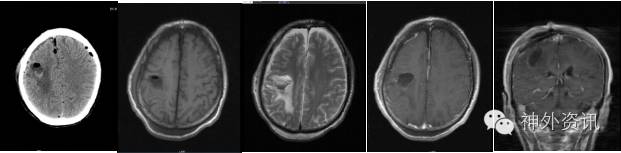

经术前科室讨论,认为患者左额顶叶病灶与临床症状有关联,病灶周围水肿明显,高级别胶质瘤可能。有明确手术指征。完善术前检查后,全麻下行开颅右侧额顶叶肿瘤切除术。术中见肿瘤上方淡黄色囊液,肿瘤呈乳白色,边界清楚,质地硬,血供一般,与周围组织粘连明显(图2)。显微镜下全切肿瘤,手术顺利。

图2. 术中见右额顶叶皮质下白色钙化状肿块,前部为淡黄色囊液。

患者术后手指麻木好转,手指活动也恢复正常。术后复查头颅CT及增强MRI,提示肿瘤全切(图3)。随访3个月,临床症状基本恢复正常。

图3. 术后头颅CT及增强MRI检查示术后改变,肿瘤全切。